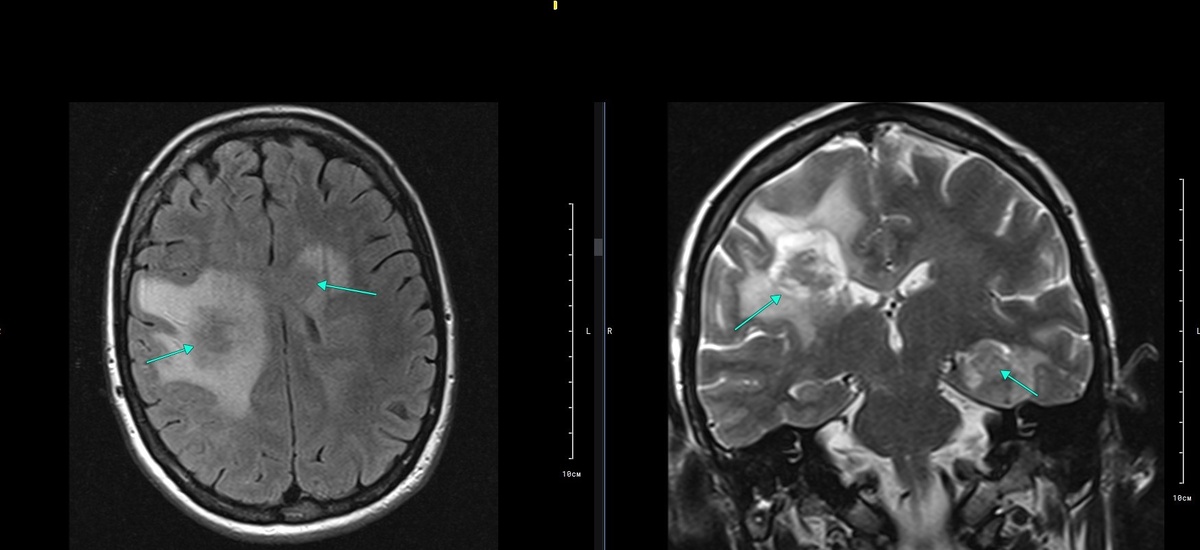

В клинику обратилась женщина Ш. 39 лет, с жалобами на слабость в левых конечностях, головокружение, общую слабость. Направлена после консультации невролога, с подозрением на ОНМК (спастический левосторонний гемипарез). Выполнено МРТ головного мозга с внутривенным контрастным усилением.

При обследовании выявлены изменения:

На границе правой лобной и правой теменной долей, с распространением в область базальных ядер справа, определяется кистозно-солидное объемное образование, неправильной округлой формы, изо-гипоинтенсивного сигнала на Т2ВИ, изо-гипоинтенсивного сигнала на Т1 ВИ, с выраженным перифокальным отеком вещества мозга, масс-эффектом в виде деформации прилежащих отделов правого бокового желудочка, примерными размерами 2,3х2,6х3,1 см.

Аналогичные образования меньших размеров определяются:

• в области базальных ядер слева, с масс-эффектом в виде компрессии левого бокового желудочка;

• на границе правых височной и затылочной долей;

• в области гиппокампов с обеих сторон (2);

• в задних отделах левой лобной доли;

• в передних отделах левой лобной доли;

• в задних отделах правой лобной доли;

• в корпусе мозолистого тела.

Субарахноидальные пространства и борозды больших полушарий неравномерно сужены на уровне образований за счет перифокального отека мозгового вещества по периферии образований. Всего визуализируемых образований 9.

Рис. 1. Т2 FLAIR аксиальная плоскость, Т2 корональная плоскость (слева направо). Стрелками в аксиальной плоскости указаны объемные образования на границе правых лобной и теменной долей, а также образование в области базальных ядер слева; в корональной плоскости – образование на границе правых лобной и теменной долей и образование в области гиппокампа слева. На Т2ВИ в корональной плоскости отчетливо визуализируется неоднородная кистозно-солидная структура, неравномерно сниженный МР сигнал и перифокальный отек по периферии образований.